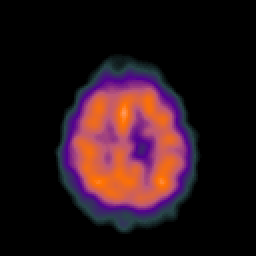

Metastatic bronchogenic carcinoma: Perfusion SPECT -- Slice #18

[Home][Help][Clinical] Slice 18